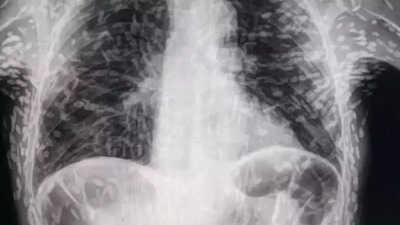

ब्राजील का रहने वाला है शख्स

ब्राजील का रहने वाला यह शख्स लगातार खांसी से इतना परेशान हो गया था कि शख्स ने सीधा अस्पताल जाने का निर्णय ले लिया था। वहां जाकर पता चला कि उसके शरीर में सैकड़ों फीताकृमि (एक प्रकार का पेट का कीड़ा) है। यह शॉकिंग खुलासा तब हुआ जब डॉक्टरों ने शख्स के शरीर का एक्स-रे किया। ब्राजील के साओ पाउलो में हॉस्पिटल दास क्लिनिकस बोटुकातु के डॉक्टर विटोर बोरिन पी. डीसूजा ने ट्विटर पर कुछ तस्वीरें शेयर की हैं। यह तस्वीरें शख्स के शरीर के स्कैन की हैं।

सिस्टीसर्कोसिस से पीड़ित था शख्स

इस स्कैन की तस्वीरों में देखकर पता चला कि शख्स सिस्टीसर्कोसिस से पीड़ित है। यह एक तरह का पोर्क टेपवर्म का ऊतक संक्रमण है। आमतौर पर यह संक्रमण मानव मल से दूषित खाना खाने या पानी पीने से होता है। यह संक्रमण तब होता है जब इंसान टेपवर्म अंडे निगल जाता है। इसके बाद लार्वा इंसान के मांसपेशियों और मस्तिष्क में प्रवेश कर जाते हैं। इससे वहां अल्सर बन जाता है।डॉक्टर ने अपने ट्वीट के साथ कैप्शन में लिखा, 'सिस्टिसर्कोसिस टेपवर्म अंडे के अंतर्ग्रहण से प्राप्त होता है।'